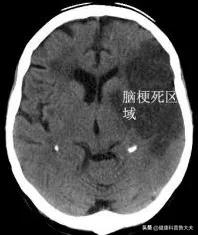

2.脳梗塞脳梗塞とは、さまざまな原因で脳への血液供給が障害され、脳組織が虚血、低酸素、壊死を起こし、対応する血液供給部位が機能不全に陥る病態である。脳梗塞の原因としては、年齢、性別、家族などの制御不能な因子に加えて、高血圧、高脂血症、高血糖、喫煙、アルコール依存症、心房細動、冠動脈疾患など、制御可能な一般的な因子が多い。高ホモシステイン血症。無症候性頸動脈狭窄症、運動不足、肥満。

統計によると、脳梗塞の5年再発率は47%以上と高く、脳梗塞の再発を防ぐには、2次予防を積極的に行い、医師の指導のもとリハビリ治療を行いながら、自己の生活管理を徹底することが最も重要である。